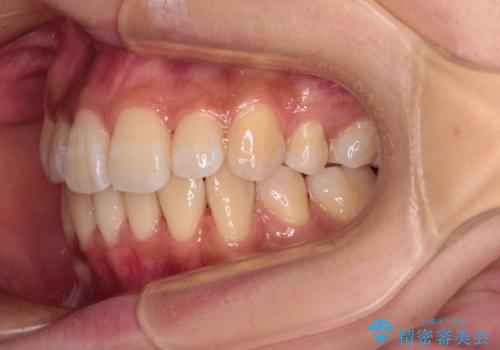

- 前歯のデコボコやクロスバイトと上顎の前突感による口の閉じにくさを気にして来院された患者様です。

目立たない装置を希望されたので、上顎が裏側装置のハーフリンガルを選択し、上下左右の小臼歯(計4歯)を抜歯して矯正治療を行うこととしました。